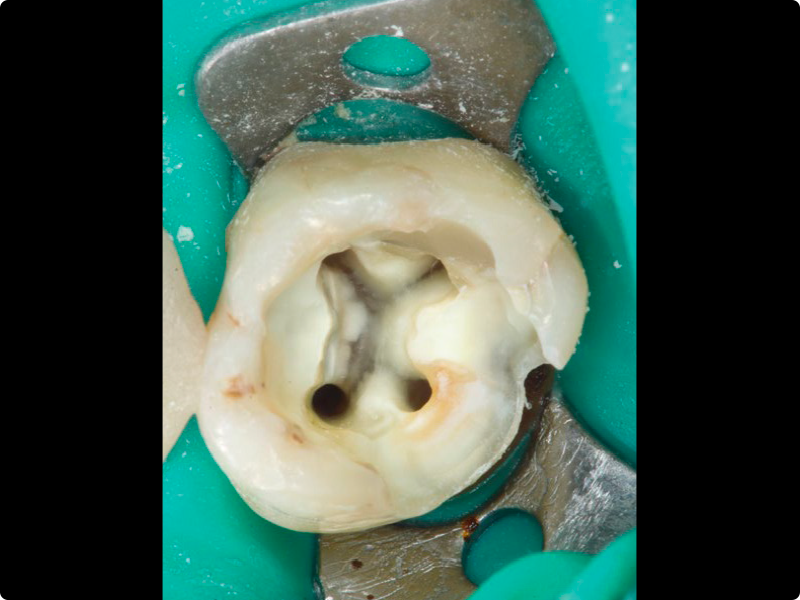

• Mechanical shaping of the canal body in continuous rotation and reciprocation, with apical finishing on extracted teeth with pre-prepared access cavities (preferably with curved canals)

• Very complex retreatments: protocols and clinical approach (Part 2)

• Altered anatomies and iatrogenic damage: operative protocols for managing root resorptions, perforations and large apical openings

• Retreatment of the teeth obturated during the previous hands-on session